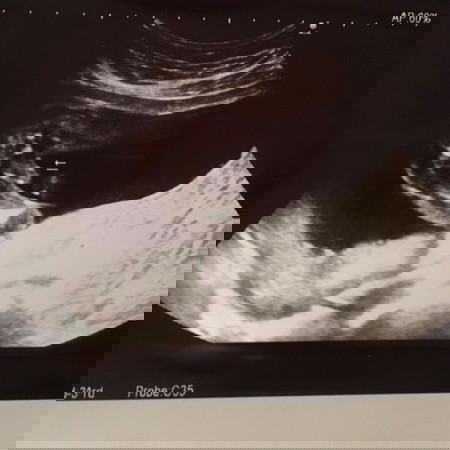

แม่ๆช่วยดูหน่อยได้ไหมค่ะ ว่า ผญ หรือ ผช 🤣 ตอนซาวด์น้องอายุครรภ์ 20 สัปดาห์ 5 วันค่ะ

คิดว่าชายนะคะ เหมือนน้องมีจู๋ระหว่างขา แม่บ้านนี้ตอนที่ซาวก็เป็นแบบนี้จ้าน้องผู้ชาย ตอนนี้ผ่าคลอดได้4วันละจ้า

ชายแน่เลยค่ะมาเต็มจอ

555 ไข่ใหญ่เต็มจอ ขอบคุณมากๆนะคะ

น้องมีจู๋😂😅